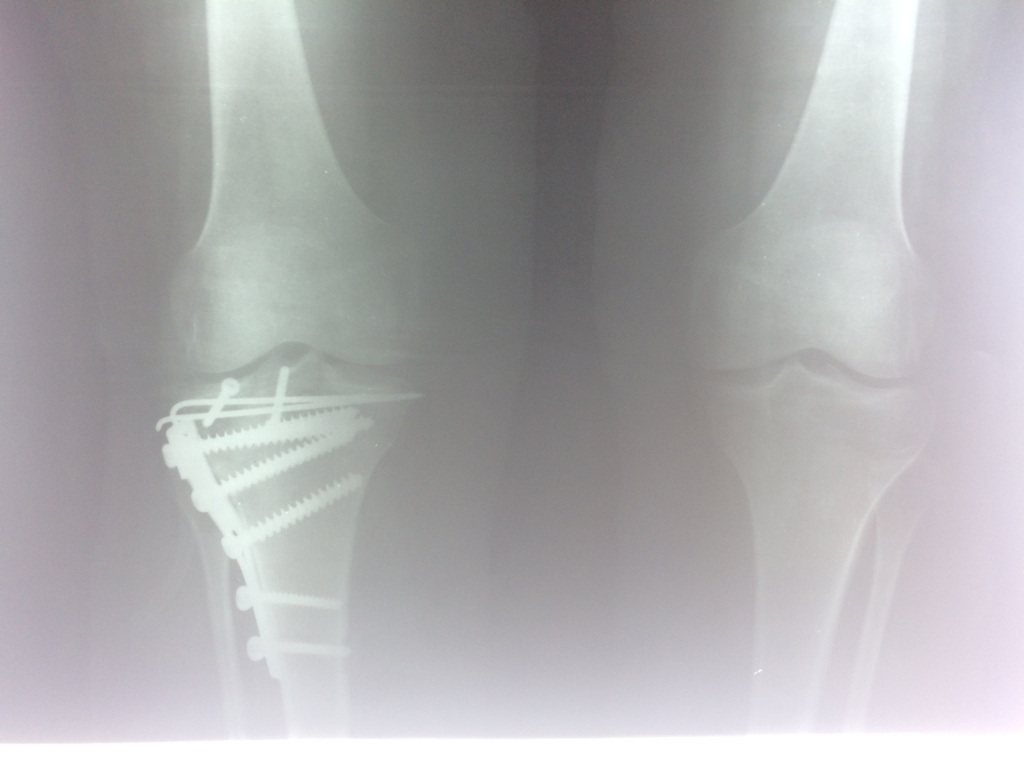

Использование материала Остеоматрикс при импрессионном оскольчатом переломе наружного мыщелка большеберцовой кости по типу Schatzker II

Использование материала Остеоматрикс при импрессионном оскольчатом переломе наружного мыщелка большеберцовой кости по типу Schatzker II.

Операция - открытая репозиция, остеосинтез большеберцовой кости опорной пластиной с костной ксенопластикой маетриалом "Остеоматрикс". На контрольных снимках в три и шесть месяцев имеется консолидация перелома, миграции фиксатора нет, имеется остеоинтеграция ксенопластического материала. Функция коленного сустава полная.